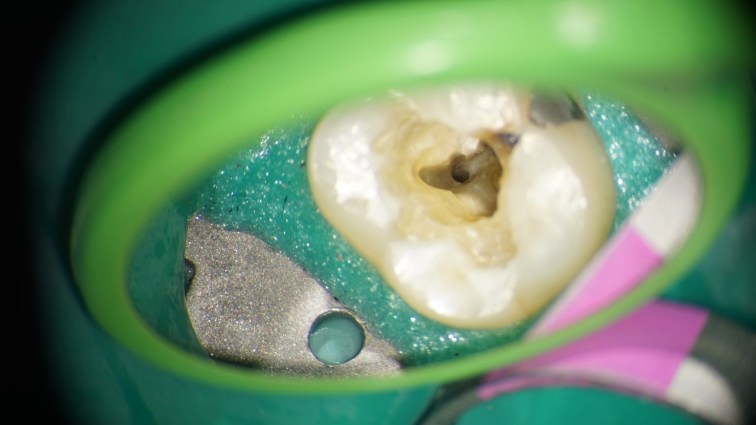

This is a “garden variety” endo. The best time to refer a case to an endodontist with a microscope is before the pulp has been touched. That way, the endodontist can control how much of tooth structure is removed to complete the endo. In this case, I had to chase all the cracks before restoring